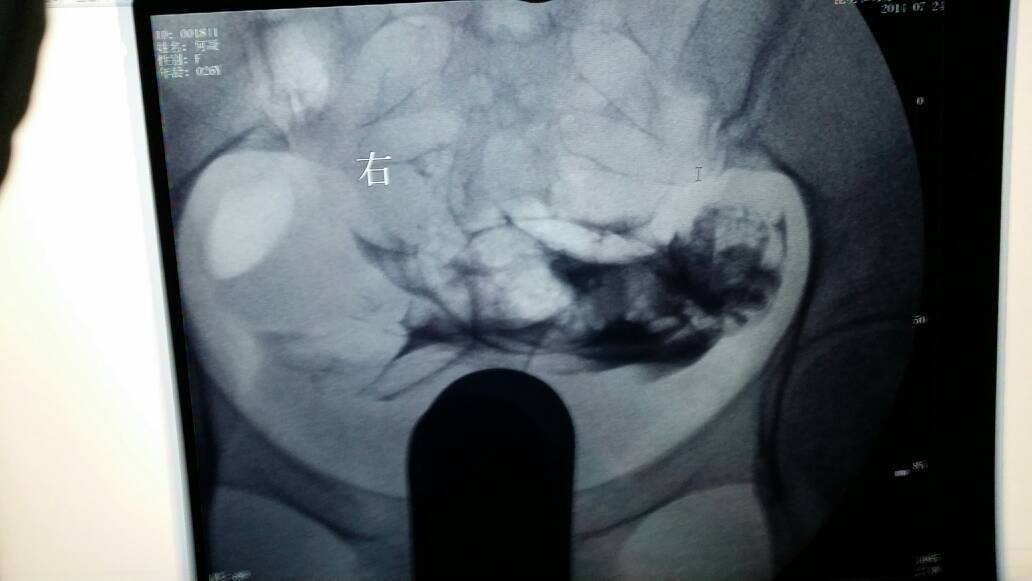

麻烦谁帮我看看输卵管造影的片子 非常感谢 点击展开 匿名用户 2014-07-24 18:14 满意回答 真心看不懂,不好意思 匿名用户 2014-07-24 18:16 宝宝知道提示您:回答为网友贡献,仅供参考。 相关问题 刚拿到输卵管造影的片子 麻烦帮我看下 今天去取了造影报告,上面是这样写的!麻烦这位亲懂的指点一下有没有什么问题的啊!好想要宝宝一直没有怀上,急啊!下面是检查报告和片子,请大家帮我看看 急急急,麻烦小儿骨科的大夫帮我看看片子,如何合适的为小儿的粉碎性骨折做出更适合的治疗,非常感谢!